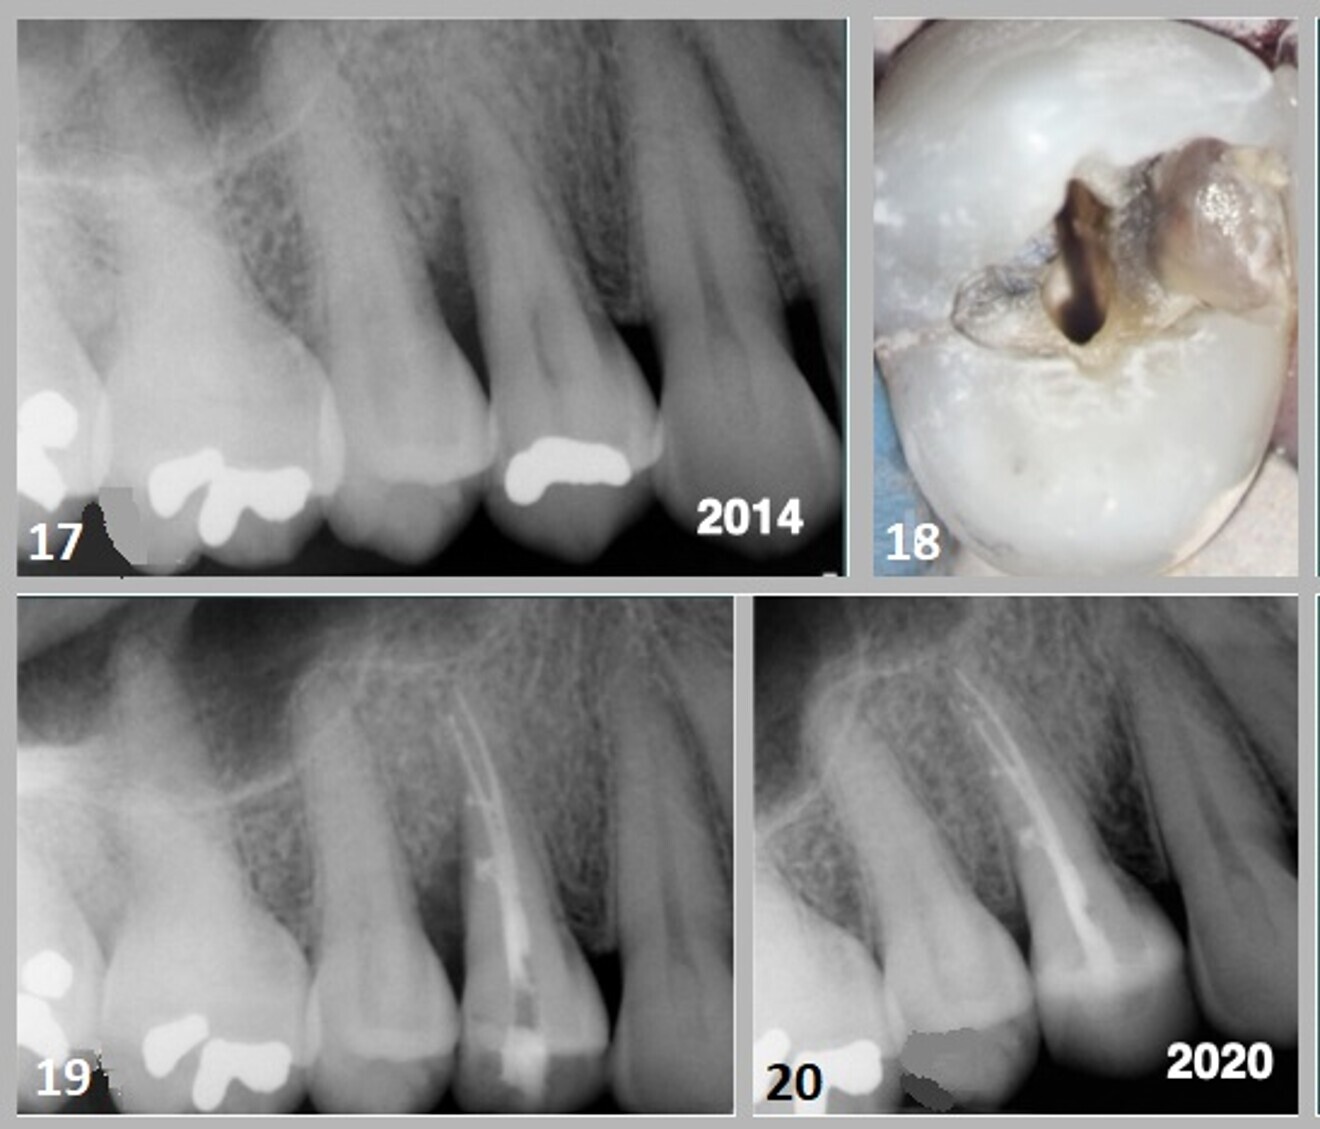

In July 2014, a 45-year-old female patient presented to the office with the chief complaint of swelling in the distal papilla of tooth #14 for a period of ten days. Clinical examination revealed an occlusal amalgam restoration with a probeable seam in the distal marginal ridge. The probing depths along the distobuccal and lingual line angles of the tooth demonstrated an infrabony pocket of 8 mm. The periapical radiograph showed a small amalgam restoration with a vertically angulated radiolucency interproximally between tooth #14 and tooth #15. A fracture line extending into the mesial marginal ridge was identified (Figs. 17 & 18). The tooth was assessed for vitality with thermal and electric pulp tests, which elicited no response.

Endodontic therapy was performed using a warm vertical condensation technique (Fig. 19). The access preparation was sealed with a flowable and hybrid composite restoration using the Bioclear Matrix system developed by Dr David Clark. The radiograph taken at a six-year follow-up (2020) showed osseous regeneration in the interproximal area, which had eliminated the periodontal defect (Fig. 20).

Case 4—Fig. 17: An 8mm infrabony defect was evident along the distal proximal aspect of the root of tooth #15. Fig. 18: Debris present in the distal marginal ridge of the tooth #14 demonstrated a fracture line; however, there was no indication of cuspal separation. Removal of the amalgam revealed extension of the fracture into the cuspal stress plane of the buccal and axial line angle. Fig. 19: The root canal space was obturated using a warm vertical condensation technique. Lateral branches of the root canal system were noted. Fig. 20: A post-op periapical radiograph taken in 2020 showed osseous regeneration and reformation of the periodontal ligament in the infrabony defect along the distal aspect of the root.